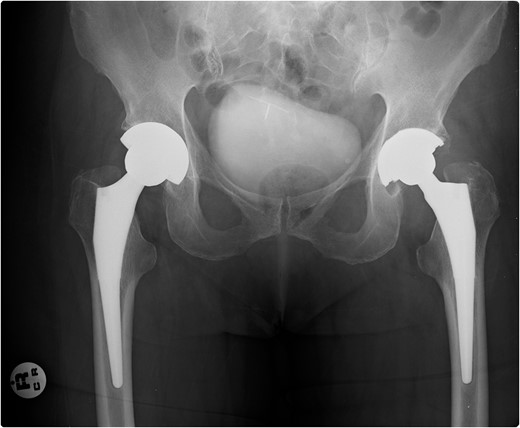

A 69-year-old female with a history of bilateral total hip replacements presented with rigors, fever and sudden onset left groin pain. A pelvic X-ray showed well-fixed implants. Blood results revealed a leucocytosis (white cell count 22.3 × 109 l–1) and elevated C-reactive protein (211 mg/l). Ultrasound-guided aspiration of her left hip grew Streptococcus gordonii. No source infection could be identified apart from a new chronic sinus infection in a left upper incisor. Following a discussion with the patient a 6-week course of intravenous ceftriaxone was started and was successful in normalizing her inflammatory markers. She was placed on long-term suppressive amoxicillin following this. Her suppressive antibiotic therapy was complicated by the development of a clostridium difficile infection and her antibiotics were changed to doxycycline. At 1-year follow-up, she was asymptomatic with no further episodes of groin pain or fever.

Prosthetic joint infection (PJI) following total hip replacement (THR) occurs in 1–2% of procedures but is one of the primary reasons for prosthesis revision (1). We report the only case of Streptococcus gordonii, a member of the viridans group streptococci (VGS), causing PJI in the setting of THR.